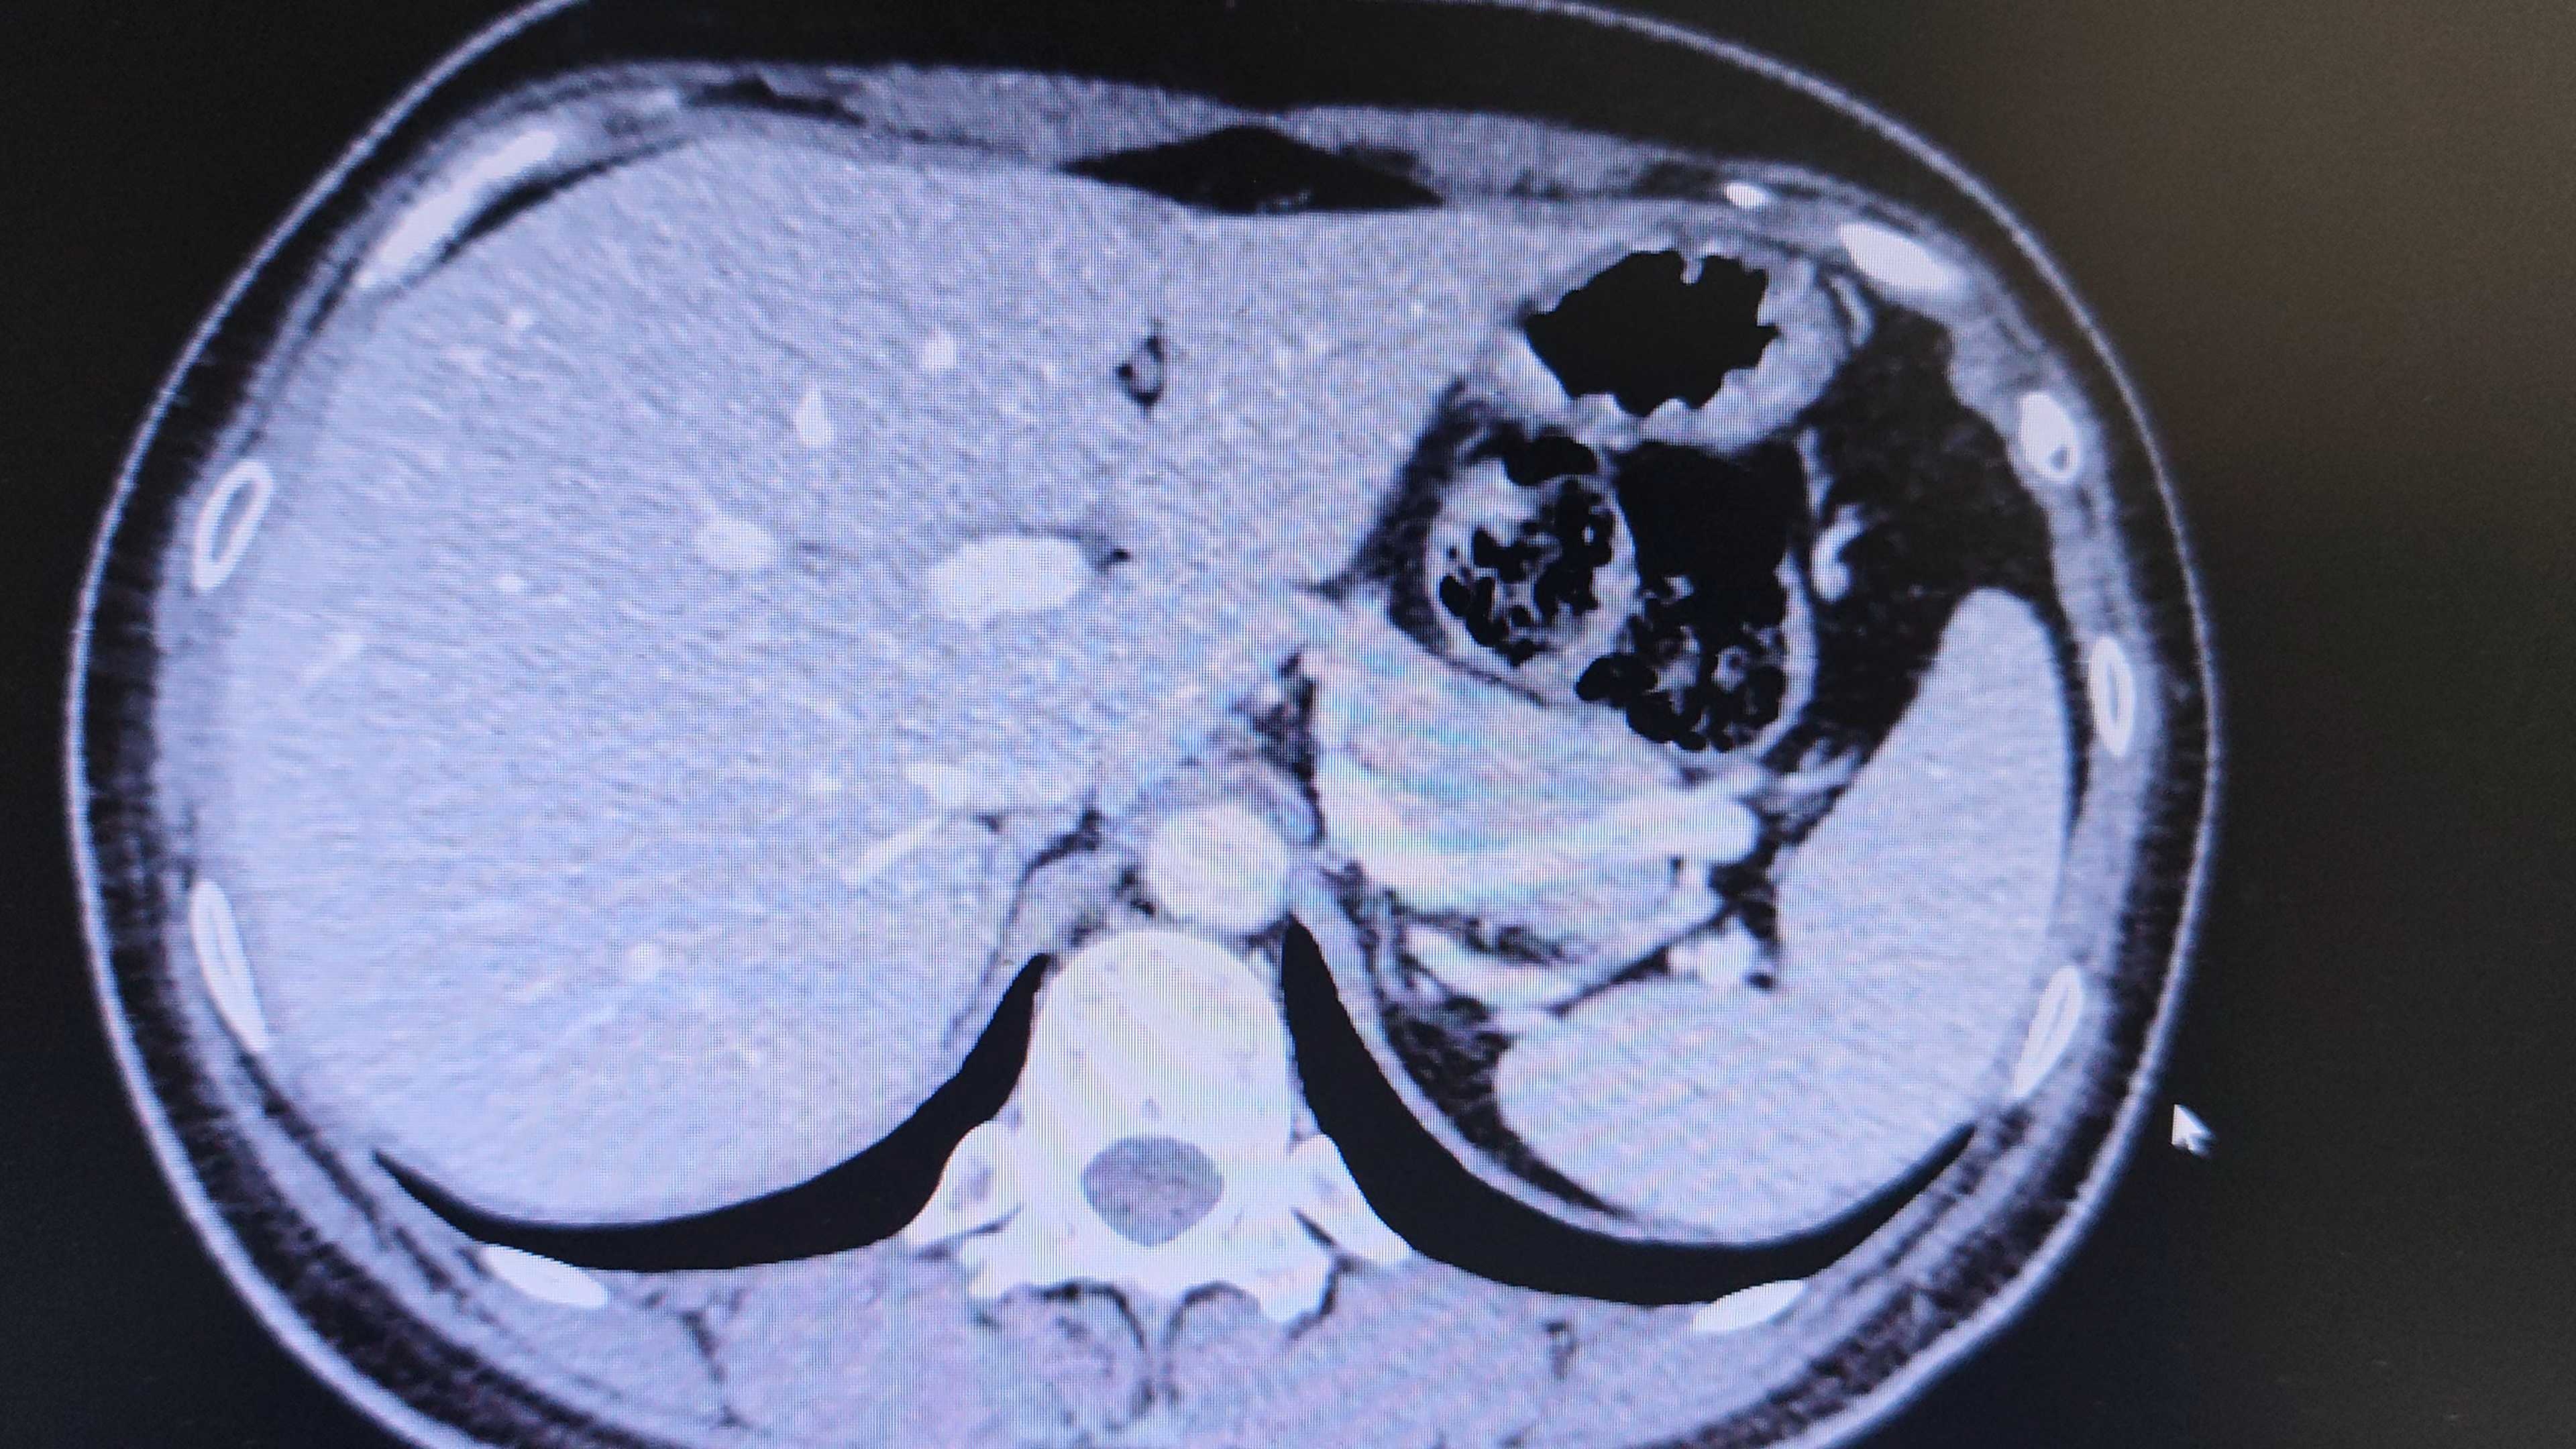

患者,女,43岁,体检发现肾肿瘤3天。

增强CT检查

肾部分切还是根治。